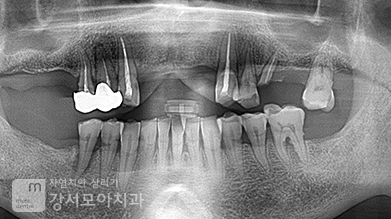

왼쪽 위아래 어금니쪽 염증이 아주 심했던 사례로

치아가 심하게 흔들리고

윗치아는 상악동, 아랫 치아는 하치조신경이라는 신경관까지

염증이 존재하였던 고난도 임플란트 케이스입니다.

뼈가 많이 녹아있었고 뿌리 부분 윗쪽으로

cyst(낭)라는 구조체 존재하였던 고난도 임플란트 케이스입니다.

오른쪽은 맨 끝 치아,

왼쪽은 큰어금니 2개가 흔들림이 심하여 발치하였으며,

심한 염증을 가라앉히고 뼈의 양이 적어

임플란트 주변 뼈를 형성하였습니다.

전신질환이 있으셔서 이 부분을 고려하여 식립하였습니다.

* 임플란트 시술 시 교합이상, 신경손상, 염증 등의 부작용이 발생할 수 있습니다. * 개인의 구강 및 치아상태에 따라 치료방법과 수가가 변동될 수 있습니다. * 해당 사례는 의료법 제56조2항을 준수하여 작성되었습니다. * 본원에서 진료받은 환자이며 전후 사진의 인물이 동일인임을 밝힙니다.